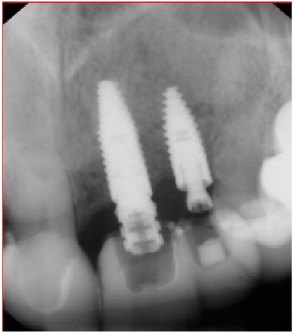

Using bilateral papillae sparing releasing incisions at surgical sites, the Cytoplast® membranes and tacks were removed and the implant sites were prepared showing excellent bone regeneration (Figures 20, Figure 21, and Figure 22). Standard protocol was used to prepare Straumann® Bone Level Tapered implants (Andover, MA, USA). (Figures 20 and Figure 22). Four months post implant placements with all 3 implants osseointegrated and provisional restorations in place. (Figures 23, Figure 24, and Figure 25).

Figure 22: Straumann Bone Level Tapered implants placed at the #s 9 and 10 sites. View Figure 22

Figure 25: 4-month post-op implant placement #10, implant osseointegrated, provisional restoration in place. View Figure 25